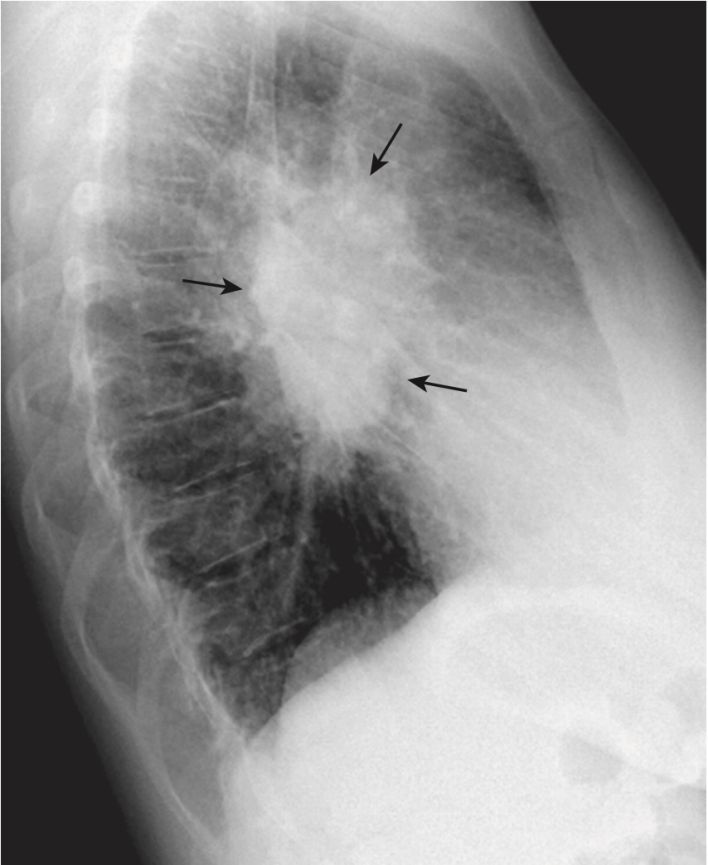

Các rãnh liên thuỳ

- Trên phim nghiêng, có thể nhìn thấy cả rãnh lớn (chéo) và bé (ngang) dưới dạng các đường nhỏ, màu trắng (dày khoảng bằng đường kẻ bằng đầu bút chì). Các rãnh phân định các thùy trên và dưới ở bên trái và các thùy trên, giữa và dưới ở bên phải.

- Các rãnh lớn chạy theo hướng chéo, khoảng từ mức của đốt sống ngực thứ 5 đến một điểm trên bề mặt cơ hoành của màng phổi sau xương ức vài cm. Rãnh bé nằm ngang mức xương sườn thứ 4 trước (chỉ có ở bên phải) và hướng theo chiều ngang (xem Hình 3).

- Có thể nhìn thấy cả rãnh lớn và rãnh bé trên phim nghiêng, nhưng do mặt phẳng chéo của rãnh lớn nên thường chỉ có thể nhìn thấy rãnh bé trên phim thẳng.

- Khi một rãnh chứa chất dịch hoặc bị xơ hóa do một quá trình mãn tính, rãnh sẽ dày lên (Hình 8). Rãnh dày lên do dịch hầu như luôn kèm theo các dấu hiệu khác của dịch trong lồng ngực, chẳng hạn như các đường Kerley B và tràn dịch màng phổi. Rãnh dày lên do xơ hóa là nguyên nhân có nhiều khả năng hơn nếu không có các dấu hiệu khác của chất dịch trong ngực.